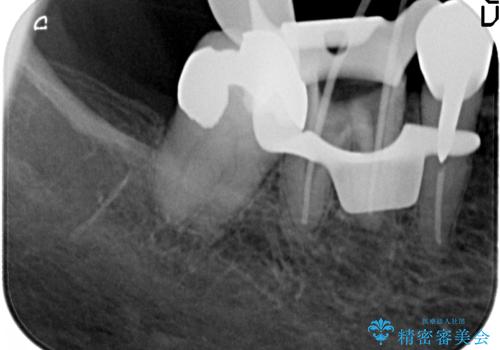

大臼歯 再根管治療

- 銀歯を白くしたいとの希望で来院されました。

せっかく銀歯を白くしても後々根管治療が必要になり、また壊して再治療を行うことを避けたいとの事でしたので、再根管治療から行っていきます。

ただ銀歯を白くするのではなく長期的な予後には歯の内部、根管治療の成功が必要不可欠です。